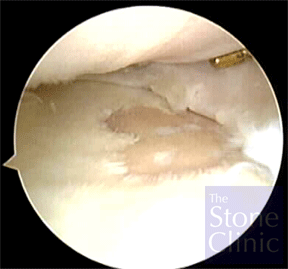

Microfracture was performed on an eburnated (lacking articular cartilage) area on the tibial plateau. The photo on the left shows the exposed bone where cartilage has been lost. The photo on the right shows the same area where microfracture is being performed by 'picking' through the surface to expose the bone marrow.